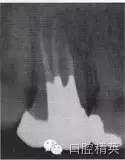

患牙根管的數(shù)目、位置以及根管的彎曲度和彎曲方向,也是影響外形制備的重要因素。為了使根管預(yù)備器械在無干擾的情況下進(jìn)入每一個根管,洞壁經(jīng)常被延長,入口的外形就隨之發(fā)生改變(圖4-2、3)。

圖4-2 洞壁被延長

A.術(shù)前X線片

B.洞壁被延長

C.根充及全冠修復(fù)

圖4-3 延長洞壁的病例